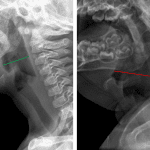

Age: 8 months

Sex: Male

Indication: Stridor

- Loss of shouldering of the subglottic airway

- Ballooning of the hypopharynx

- Croup (laryngotracheobronchitis)

Loss of shouldering of the subglottic airway and ballooning of the hypopharynx, likely relating to croup.

No evidence of epiglottitis.

No retropharyngeal thickening.